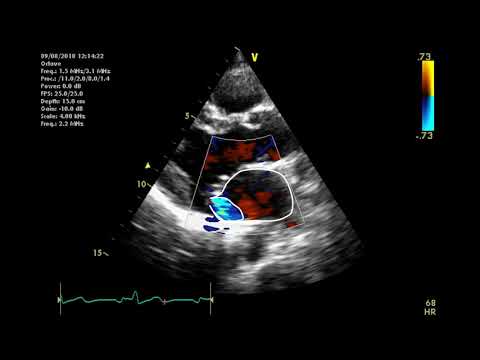

Как использовать LVOT VTI для определения реакции на инфузионную терапию у пациентов в критическо...

Автор: Мэтью Липтон, доктор медицины, член FACEP. Сертифицированный врач-специалист по неотложной помощи, прошедший обучение по программе повышения квалификации в области неотложной помощи в США, сдавший экзамен CCEeXAM и являющийся энтузиастом POCUS.